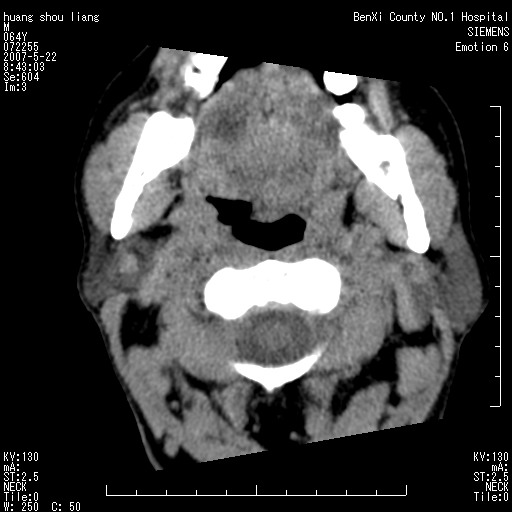

男性,64岁。颈部包块8年。最近增大。

对不起大家,可能是片子发太多有点乱,正常腮腺在下颌角的外侧,颌下腺在下颌体的中部内侧,本例在下颌角内侧偏下,和腺体一点关系都没有,从vrt和mpr上可以很明显看出来,再者肿块是好多粘连在一块的,大家在仔细看看,左侧可能也是吧,我还是考虑为肿大的淋巴结融合在一块,但性质??????

右侧腮腺下部均匀软组织密度肿块,外形不规则,与周围组织分界清晰,考虑右侧腮腺混合瘤或多形性腺瘤。

大家好,病理结果出来了,如大家所说,颌下腺混合瘤。

唉,解剖没学好吧,我诊断错了,不过还是有些不理解回去我在多看看书,谢谢大家的参与,以后我还会奉献好的病例。